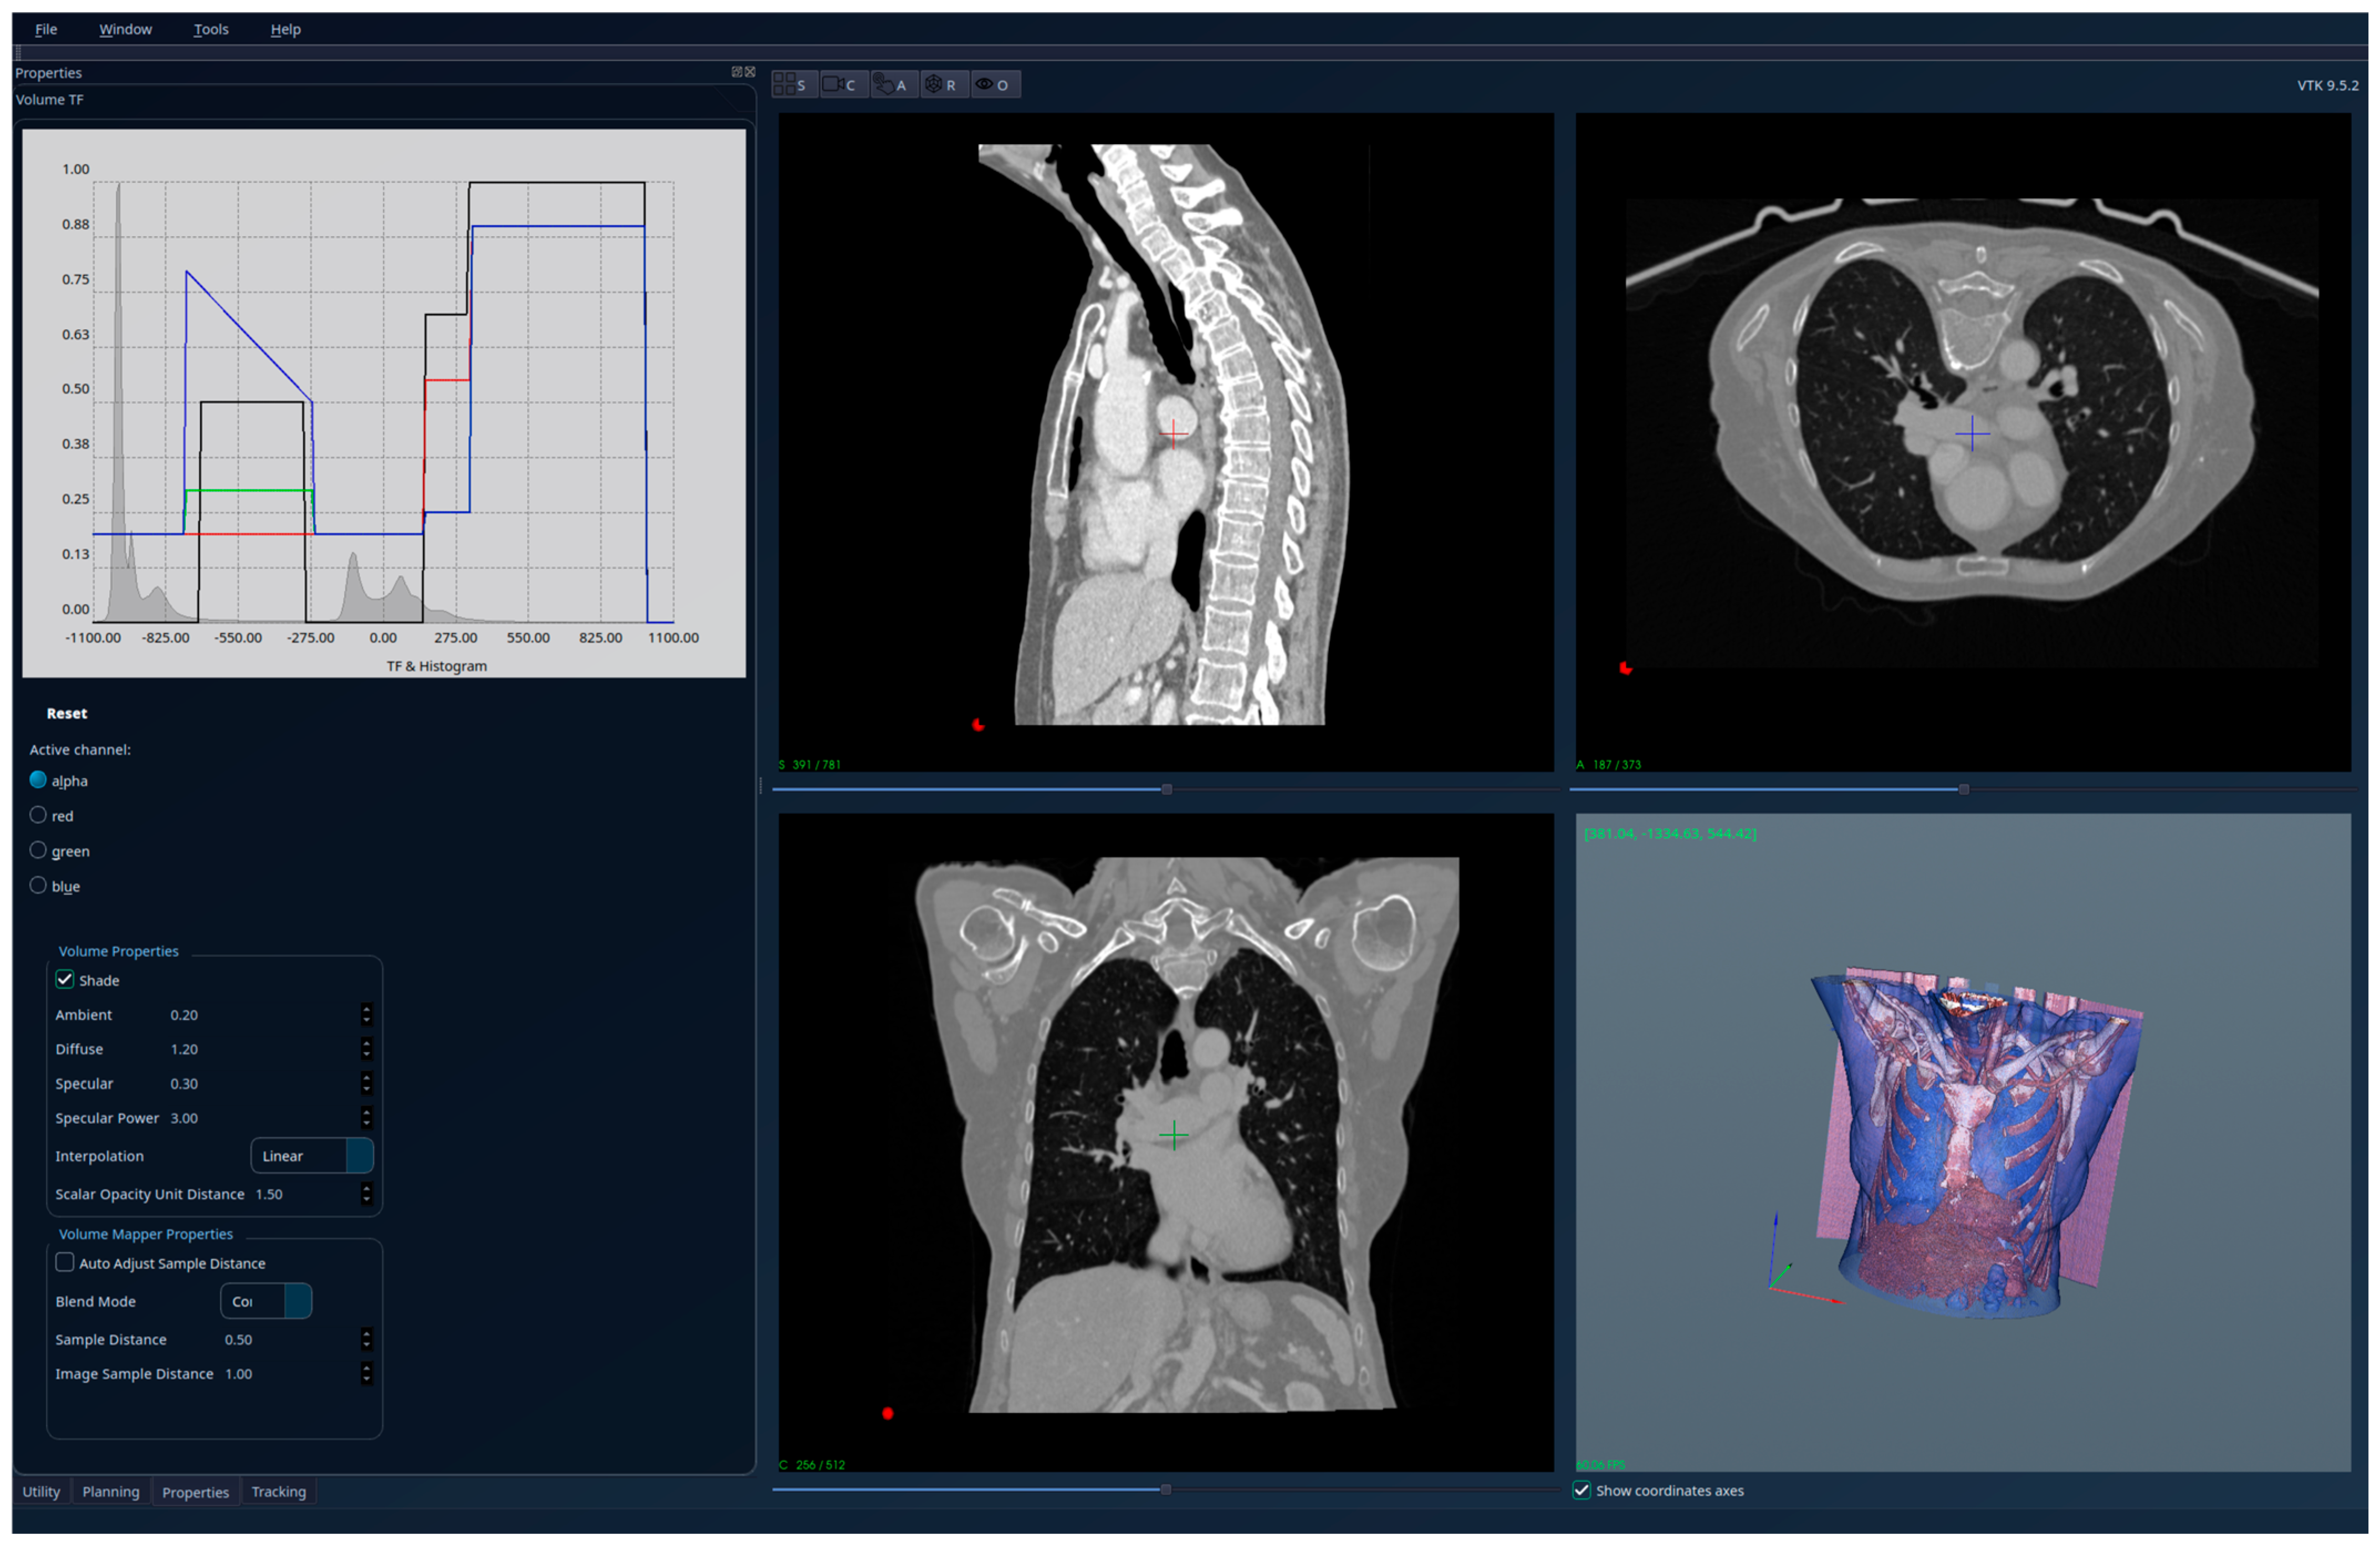

3. Results

| Patient 2 (fibrosis) | 640 × 512 × 370 | 0.6 × 0.6 × 1 | 38,113 |

| Patient 2 (fibrosis) | Br60 | 1 | Siemens Healthineers | SOMATOM go.Top |